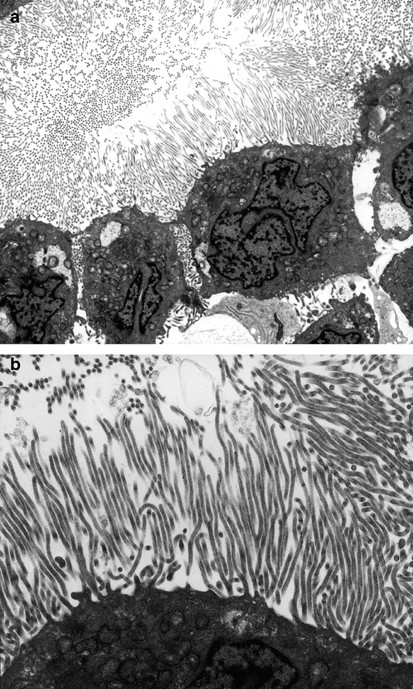

The most common ultrastructural characteristics of the mesotheliomas were the presence of long, slender, often branching, undulating microvilli on the apical surface of the cuboidal cells lining the tubules or papillae (Figure 3a, b), dilated intercellular spaces (Figures 3a and 4), and intracellular lumens (Figures 5 and 6). On occasion, a profusion of microvilli was also seen on the basal surface of the cells (Figure 7a) or involving the entire cell membrane (Figure 7b). The cytoplasm usually exhibited large amounts of intermediate filaments often arranged in bundles (Figure 8). A variable amount of glycogen was also a common finding (Figure 6). A rare cell exhibiting a single cilium was identified in three of the cases, and, in one of these, the cilium was intracytoplasmic (Figure 9).

(a) A group of mesothelioma cells showing a profusion of microvilli on their apical surface. The intercellular spaces are dilated and the lateral cell membranes are also covered by microvilli. (b) Higher magnification electron micrograph of the same case as shown in (a), showing the typical wavy appearance of the microvilli. Branching of the microvilli is also apparent (a, × 8000; b, × 20 000).

Although these mesothelioma cells do not display the same profusion of microvilli seen in the case in Figure 3a, b, the dilatation of the intercellular space together with the presence of microvilli along the lateral cell membrane support the diagnosis of mesothelioma over serous carcinoma. That the entire cell membrane seen in the lower left corner of the figure is covered by microvilli is also an indication that the tumor is a mesothelioma (× 3800).